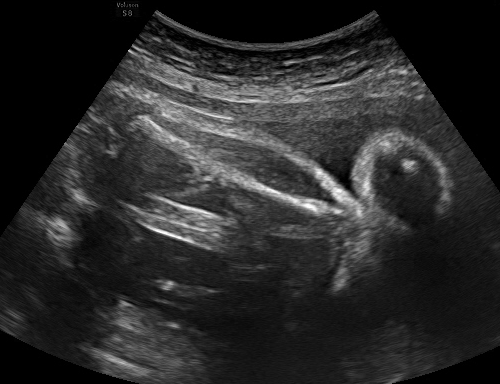

TABLE I: Sample outputs comparing reference captions with captions generated by the proposed model.

Uterine Ultrasound Image Reference Caption Generated Caption

Consequently, the CNN-BiGRU model outperformed the other baseline models regarding BLEU and ROUGE scores and demonstrated lower loss values, underscoring its effectiveness in this application. Moreover, Table I provides further evidence by illustrating sample outputs that compare reference captions with captions generated by the CNN-BiGRU model. This comparison vividly showcases the model’s ability to generate high-quality captions through its robust bidirectional processing capabilities.